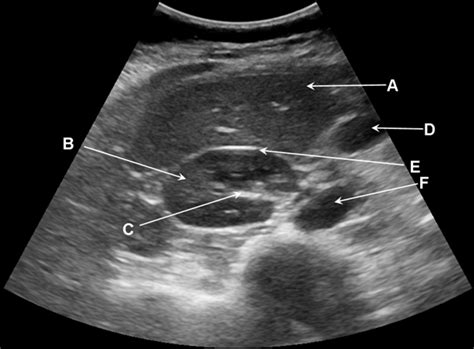

An ultrasound of abdomen is used to evaluate a wide range of conditions affecting the abdominal organs. Some of the most common uses include:

• Abdominal Aorta: Checking for aneurysms or other abnormalities in the abdominal aorta.

Interpreting the Results of an Ultrasound of Abdomen

The images obtained from an ultrasound of abdomen are reviewed by a radiologist, who provides a detailed report to the referring physician. The results can help diagnose various conditions, including:

• Abdominal Aortic Aneurysm: The presence and size of an aneurysm in the abdominal aorta can be assessed.